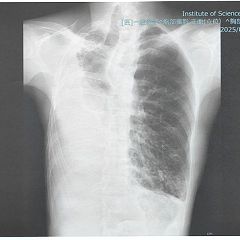

気胸で難聴、でも大丈夫

自然気胸と突発性難聴を発症したDr.Tによる体験記。入院なんて、怖くない。入院中に書いたリアル記録もあります。